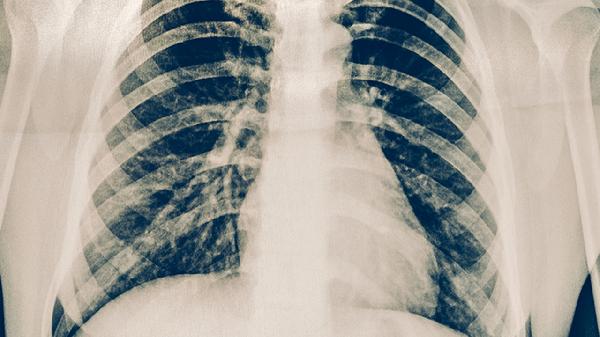

混合磨玻璃结节在CT影像中表现为部分模糊半透明、部分致密实变的病灶,其成因多样。良性可能性包括肺炎、肺结核等感染性病变,这类结节边缘多模糊且可能伴随咳嗽、低热等症状,抗感染治疗后通常缩小或消失。早期肺癌也可能呈现此类特征,尤其是实性成分占比超过50%或结节直径超过8毫米时,需警惕恶性可能。部分非感染性炎症如机化性肺炎、肺纤维化也可导致类似表现,通常需要结合肿瘤标志物、PET-CT或穿刺病理进一步鉴别。